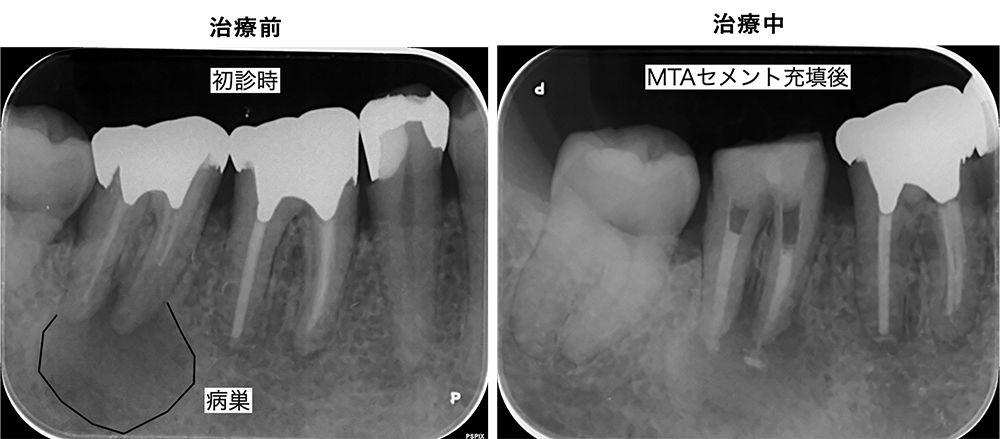

金山デンタルクリニックでは、治療の前に必ずCT撮影を行い、神経の本数や根の形、病変の大きさを正確に診査。治療の可能性や成功率まで含め、CTの画像を見せながら丁寧にご説明しています。治療後の経過もマイクロスコープやCT画像をお見せしながら、ご説明させていただきます。

当院では、マイクロスコープを完備した専用診療室で、ラバーダム下での精密根管治療を行います。

根管治療は細菌との闘いです。ほんの少しの細菌の侵入が、再感染や治癒不良につながります。だからこそ、1回1回の治療に妥協せず、徹底した衛生管理と可視化された治療を行っています。